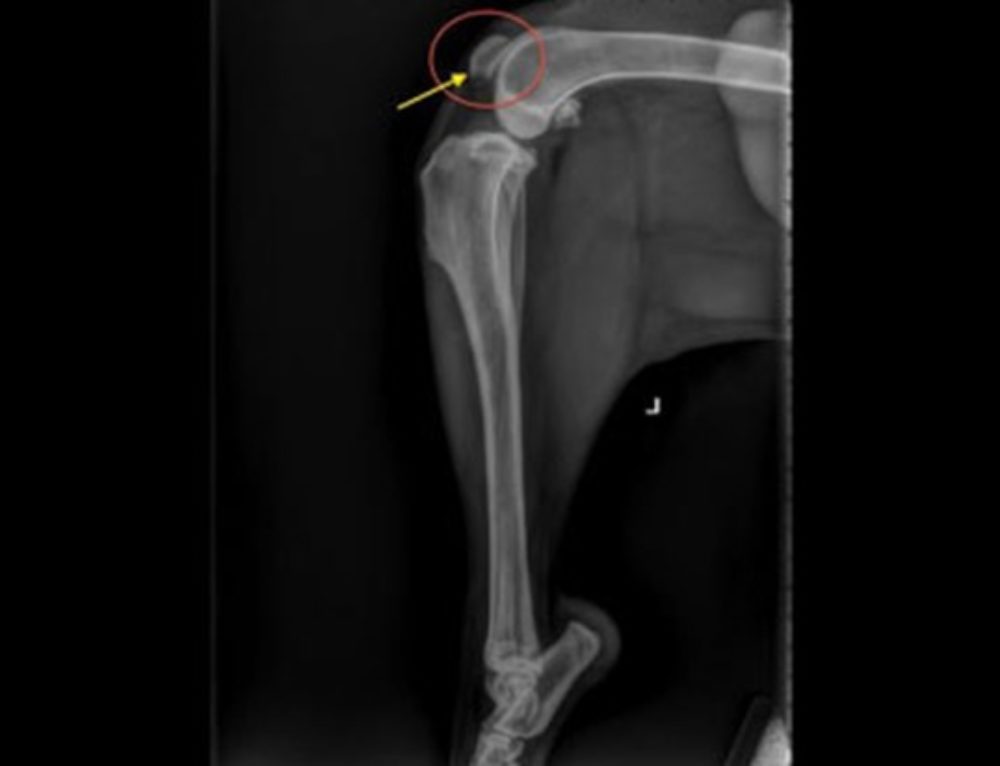

CAT FEMUR DISLOCATION XRAY Royalty Free Stock Photo Image 30050455 Cat Arm Dislocation dislocated joints are painful and uncomfortable injuries that can affect your cat’s ability to move and enjoy life. a joint dislocation is when bones in a joint pull apart and out of position. joint dislocations are paired most commonly with other serious injuries from trauma. hip dislocation is usually the result of injury or trauma that. Cat Arm Dislocation.